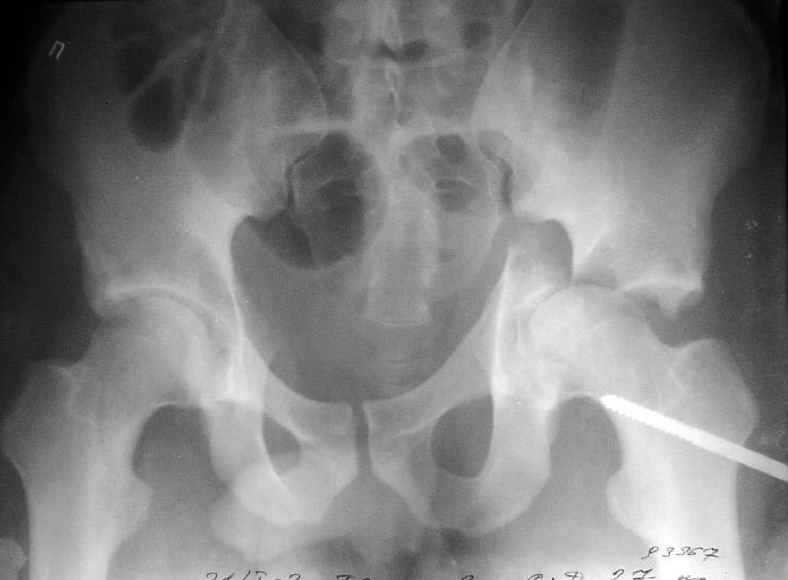

Пациент переведен в нашу клинику на 5 день после множественной травмы 25.01.2003 - двустороннее повреждение вертлужных впадин, разрыв левого крестцово-подвздошного сочленения. Вывихи обоих бедер. В месте первичного поступления подвздошный вывих правого бедра вправлен 26.01.2003, наложено вытяжение за левую вертельную область. Остеосинтез левой вертлужной впадины выполнен у нас 6.02.2003. Вопрос: надо ли синтезировать задне-верхний край правой вертлужной впадины?

правую впадину собрали здорово! Мои поздравления Рункову. Сами меня учили-учили, а где же запирательная проекция левой вертлужной

впадины. Такое впечатление что на КТ есть интерпозиция кусочком, тогда уж точно надо туда залесть, а так, я считаю не стоит.

Уважаемый Алексей, через месяц после повреждения обострять травму, чтобы продлить "колясочный" срок? Второй сустав станет опорным не скоро.Головка на Ртг концентрически вставлена, задний фрагмент не интерпонирует, лимбус,по видимому тоже, ямочный фрагмент мешать не должен,герметизирующую манжету адекватно восстановить, обычно, не удается. Выгоды от оперативного вмешательства сомнительны. Я бы оперировать не стал.Еще месяц без нагрузки (по меньшей мере) и в нашей "конторе"- МОНИКИ(Вы наверняка знаете О.Ш.Буачидзе) положились бы на ощущения пациента при активных движениях правым бедром. Можно и сейчас проверить на возможность блокады и тогда принимать окончательное решение.

Согласен, что нужна вторая проекция.